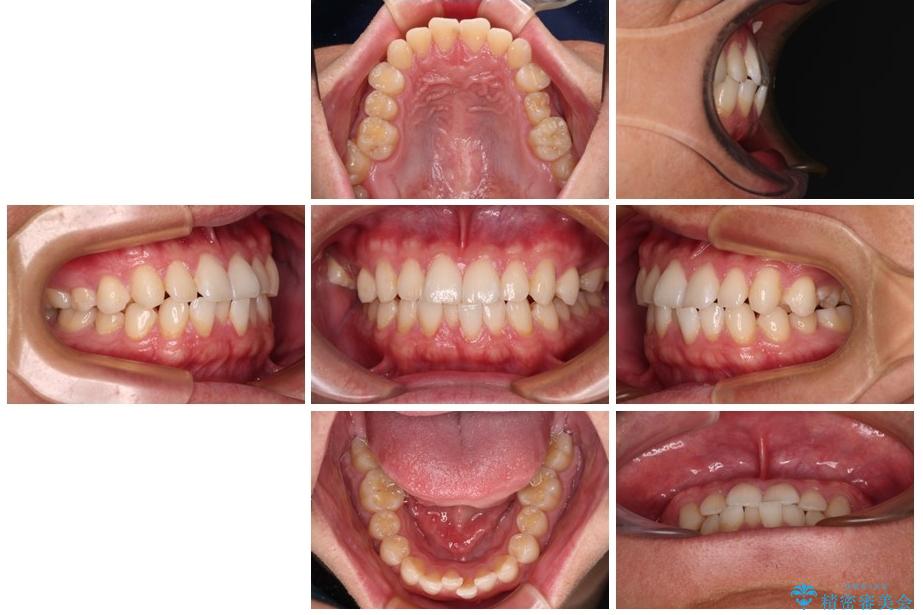

治療後

• 前歯のガタガタ・奥歯のかみ合わせ(シザーズバイト)を改善|1年半で完了したメタルブラケット矯正 治療後画像

**前歯のデコボコ(叢生)**が整い、歯列全体が美しく改善

シザーズバイトの奥歯も正常なかみ合わせに改善

捻転歯も回転が修正され、全体的に清掃性・咀嚼効率が向上